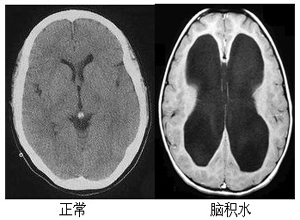

腦積水是由于顱腦疾患使得腦脊液分泌過多或循環(huán)、吸收障礙而致顱內(nèi)腦脊液量增加,腦室系統(tǒng)擴(kuò)大或蛛網(wǎng)膜下腔擴(kuò)大的一種病癥。其典型癥狀為頭痛、嘔吐、視力模糊,視神經(jīng)乳頭水腫,偶伴復(fù)視,眩暈及癲癇發(fā)作。是一種相對比較危險的疾病,那么腦積水能治好嗎?